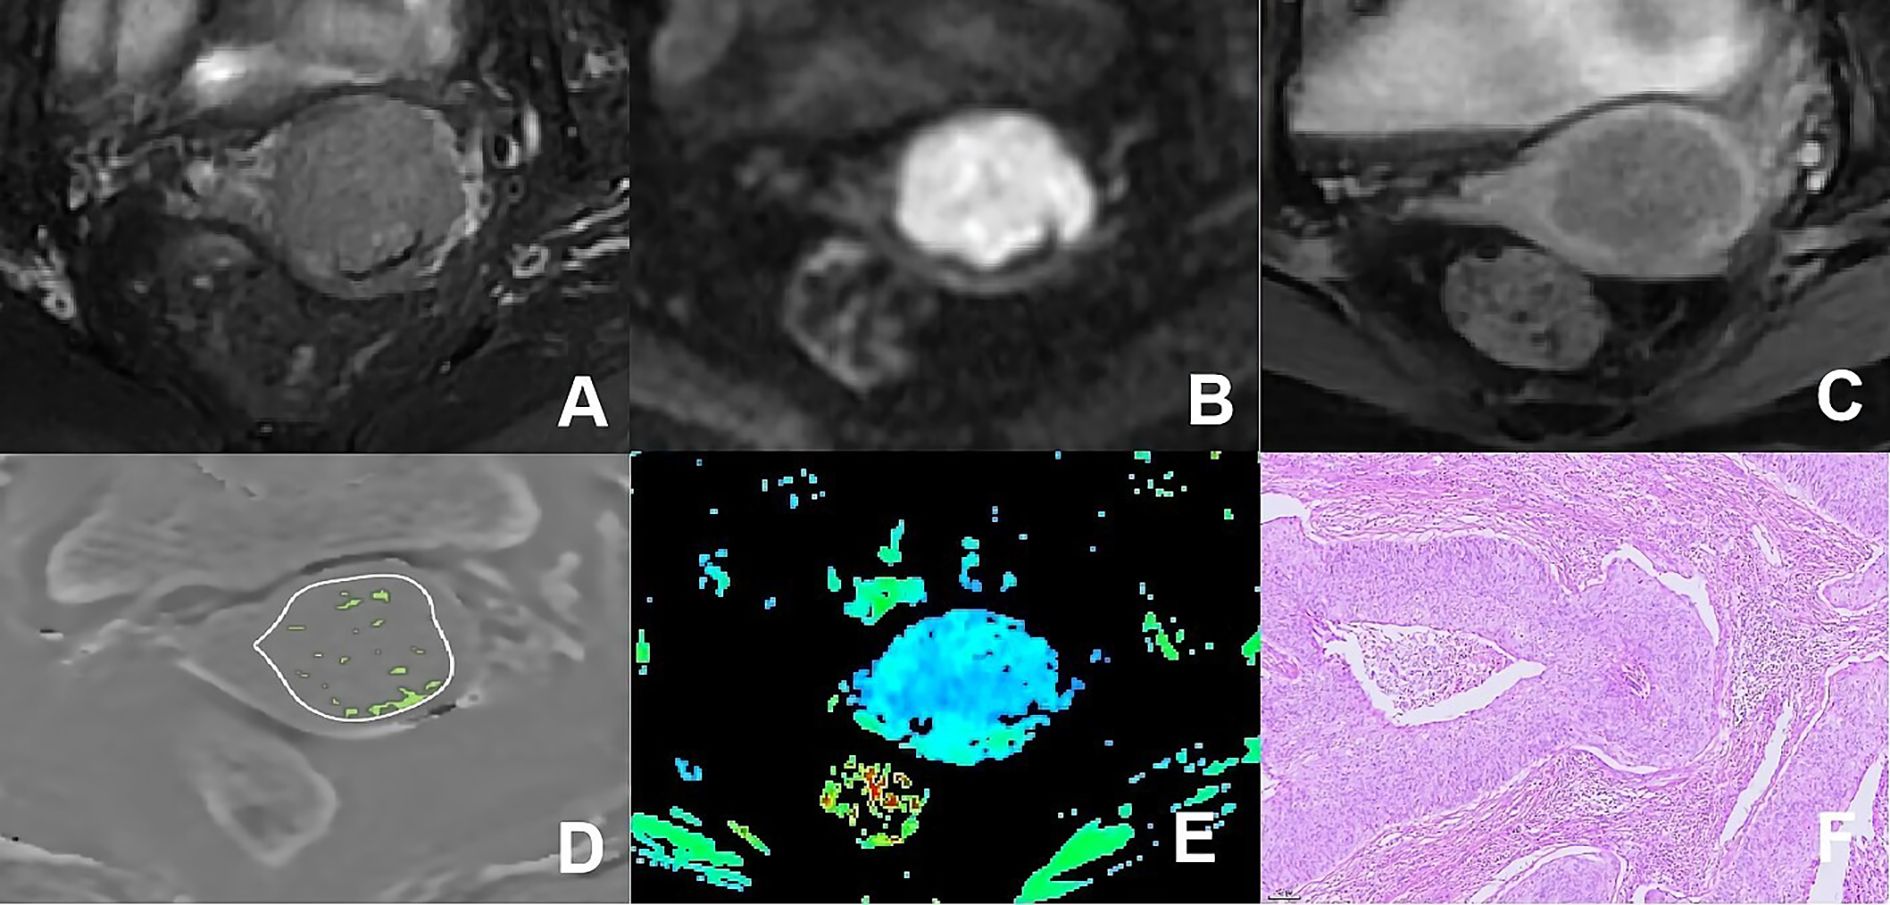

Figure 3

MRI and pathology images of a pelvic structure. A: T2-weighted MRI showing detailed anatomy. B: Diffusion-weighted MRI highlighting a bright area. C: Post-contrast MRI indicating enhancement. D: ADC map showing precise tumor margins with green highlights. E: Color-coded map displaying intensity variations, with blue and green areas. F: Histological slide showing cellular arrangement and tissue pattern.

Figure 3. (A–F) presented a 75-year-old patient diagnosed with poorly differentiated CA, classified as FIGO stage IIB. (A) Axial T2WI image: the mass demonstrated mixed iso-hyperintense signal; (B) Axial DWI image: the mass with restricted diffusion showed significant hyperintense signal; (C) Axial enhanced image of the delayed period: the mass revealed uneven hypointense signal and annular enhancement; (D) The schematic diagram illustrated the ITSS intensity measured using AS software, where the green area on the diagram signified the ITSS within the tumor, with an ITSSs of 0.204 and ITSSv of 0.229; (E) R2* map of the ESWAN sequence, where the mean value of R2* for this patient was 23.184Hz. (F) Pathological image confirmed CA.